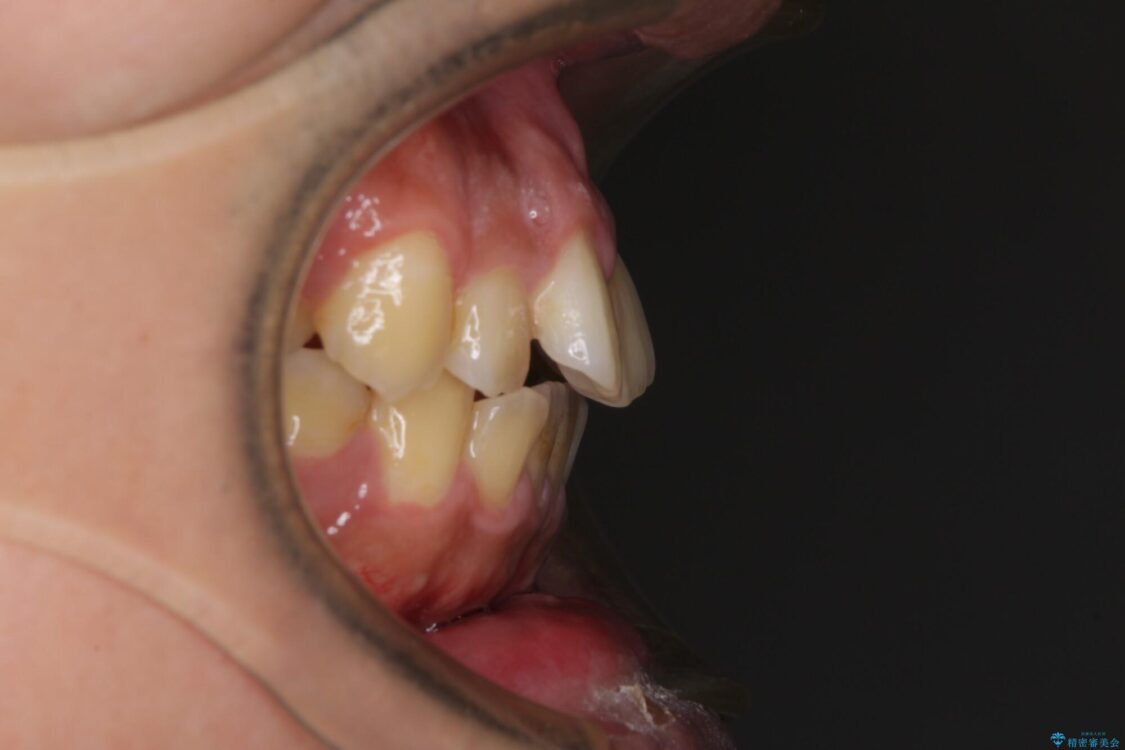

高校時代に行った抜歯矯正が後戻りをしたとのことで来院された患者様です。

下顎骨が左側に変位しているため、正中が合わないことは予想できましたが、歯列が整った後も咬み合わせが安定せず、咬み合わせを落ち着かせるために1年以上の期間を要しました。

治療前

• 後戻りでデコボコの前歯 インビザライン矯正治療 治療前画像